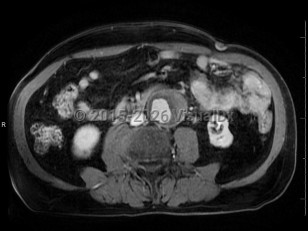

Abdominal aortic aneurysmAbdominal aortic aneurysm

Intraabdominal abscessIntraabdominal abscess